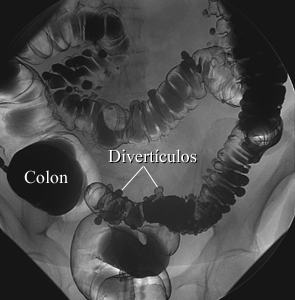

Diverticulosis

Cortesía de Intermountain Medical Imaging, Boise, Idaho. Todos los derechos reservados.

En un estudio con contraste de aire, el colon primero se llena con bario y luego se drena el bario, dejando solamente una capa delgada de bario en la pared del colon. El colon entonces se llena con aire. Esta imagen de un enema de bario muestra sacos (llamados divertículos) en la pared del colon.